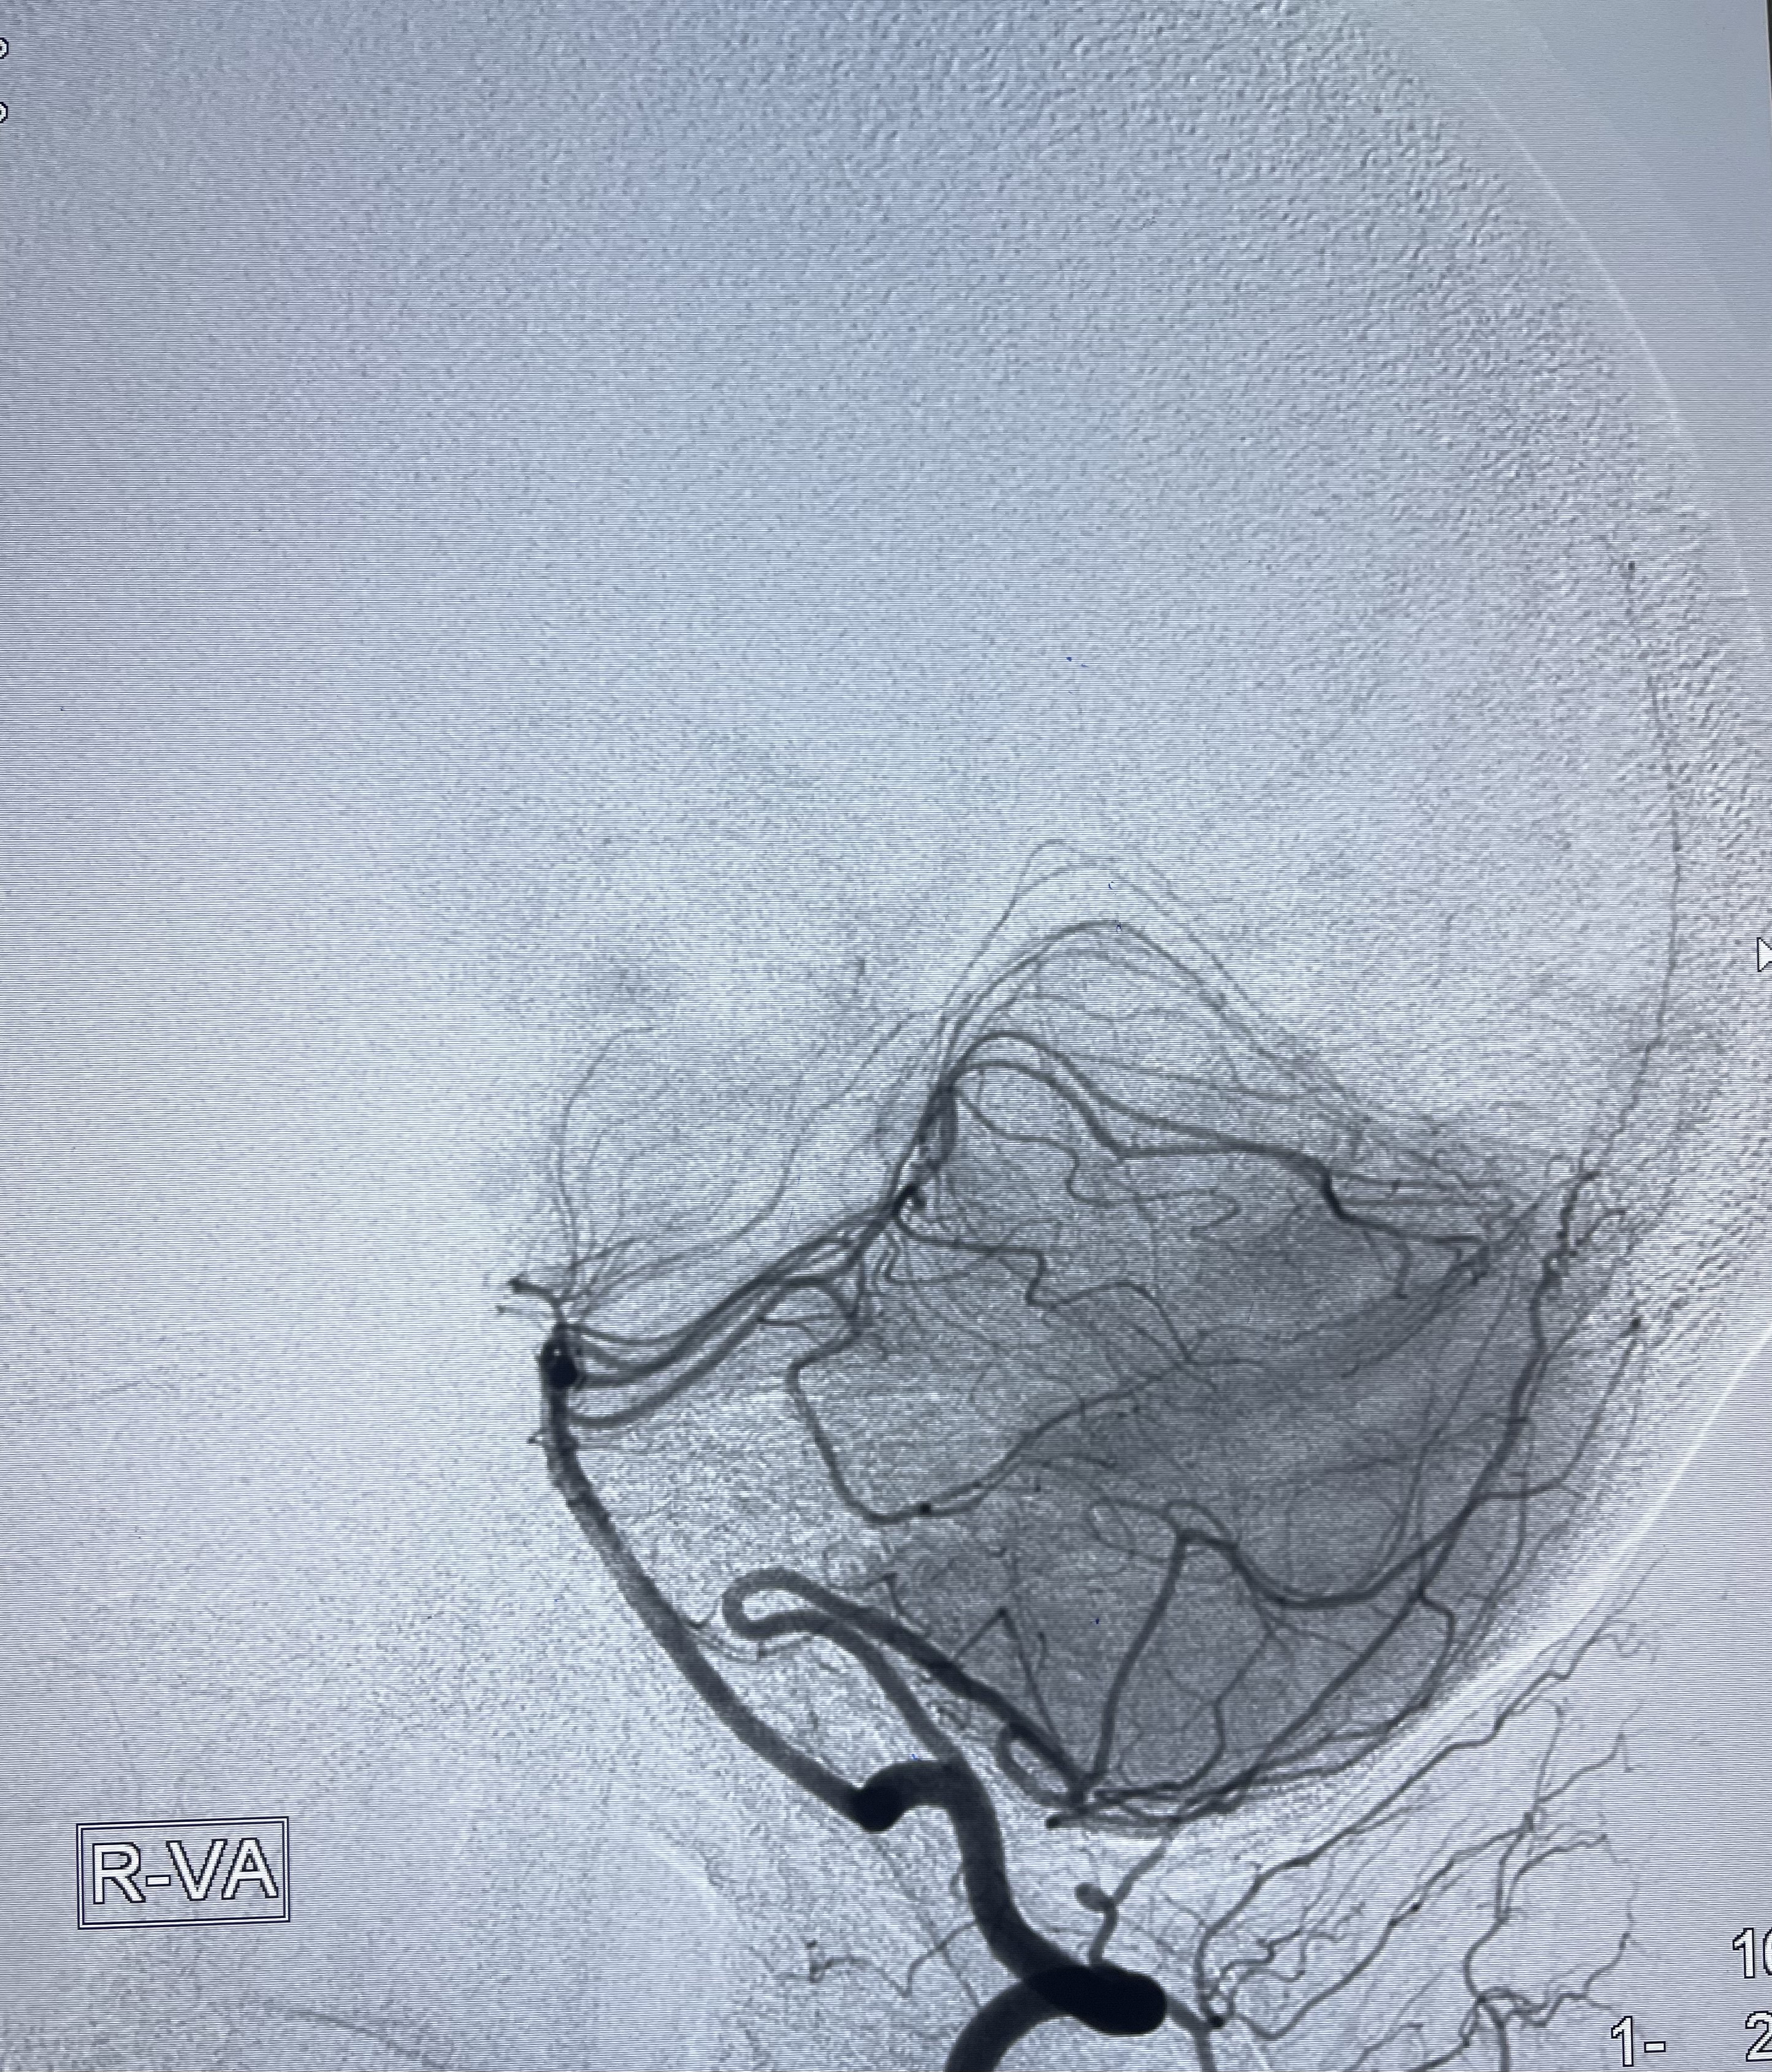

动脉瘤致密填塞

麻醉苏醒佳

术后即刻CT